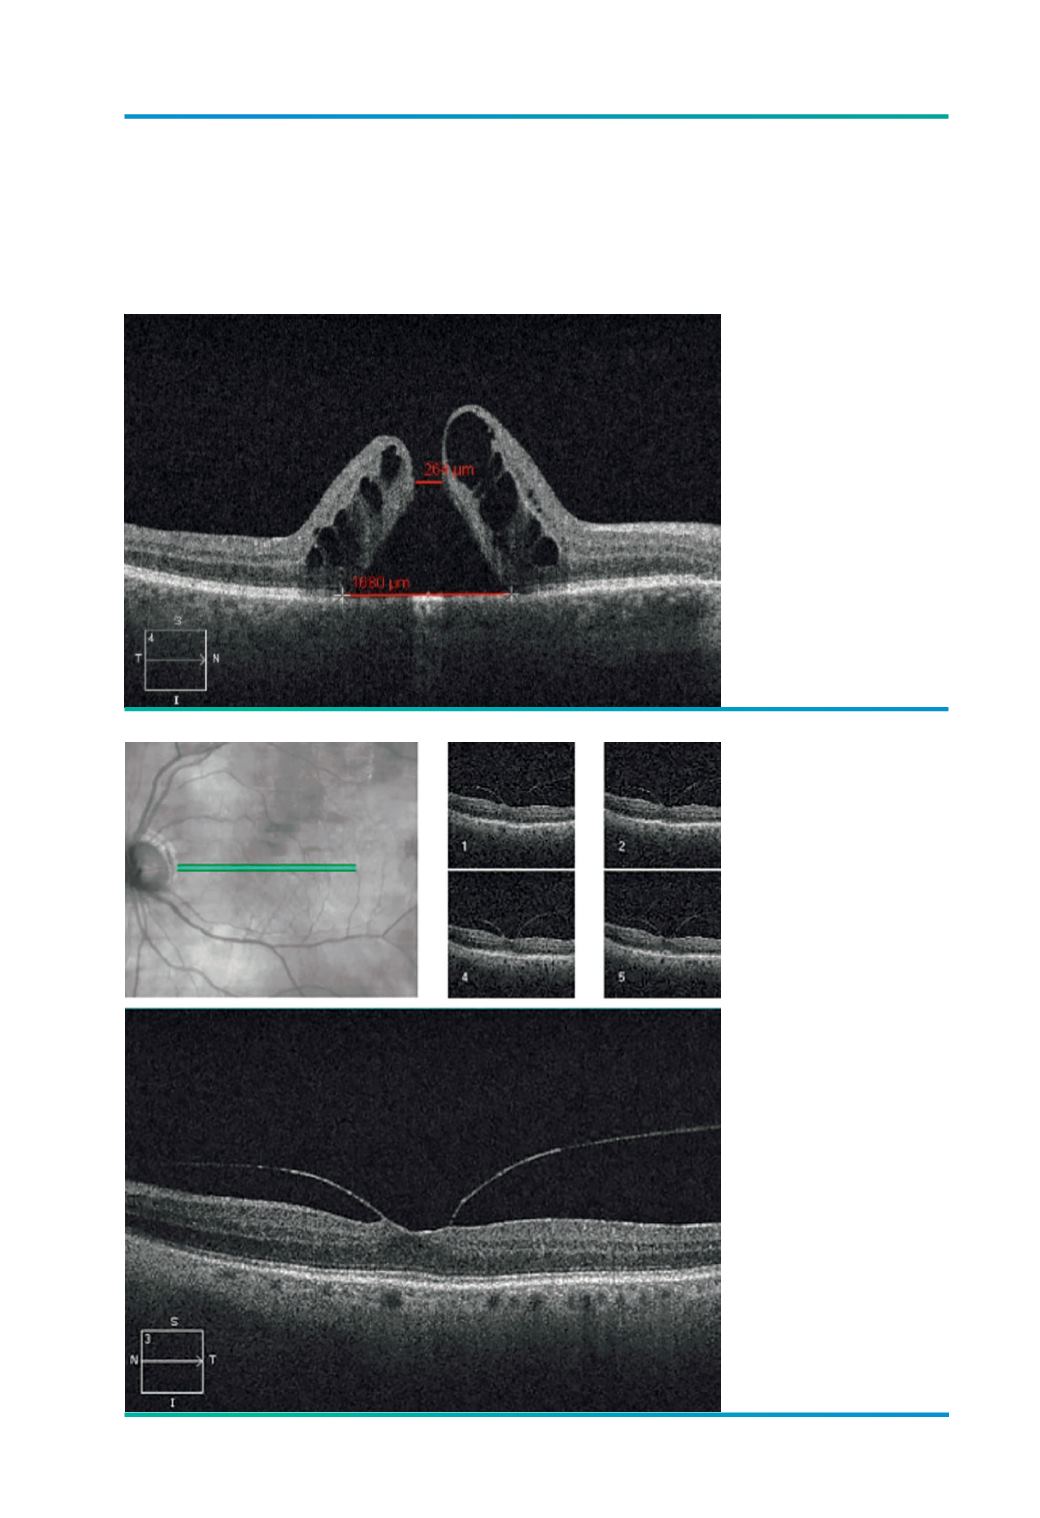

Figura 4.

Medições num buraco

macular.

Figura 5.

Raster scan – diminuição

do espaçamento.